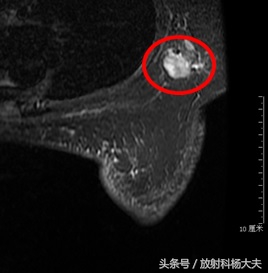

肿大的腋窝淋巴结

与此同时进行的淋巴结活检,却提示转移瘤来自乳腺(穿刺的病理:只是提示,没法百分之百)!

由于当地医院没法做乳腺MR,患者来到了北京,我们给做了乳腺MR。